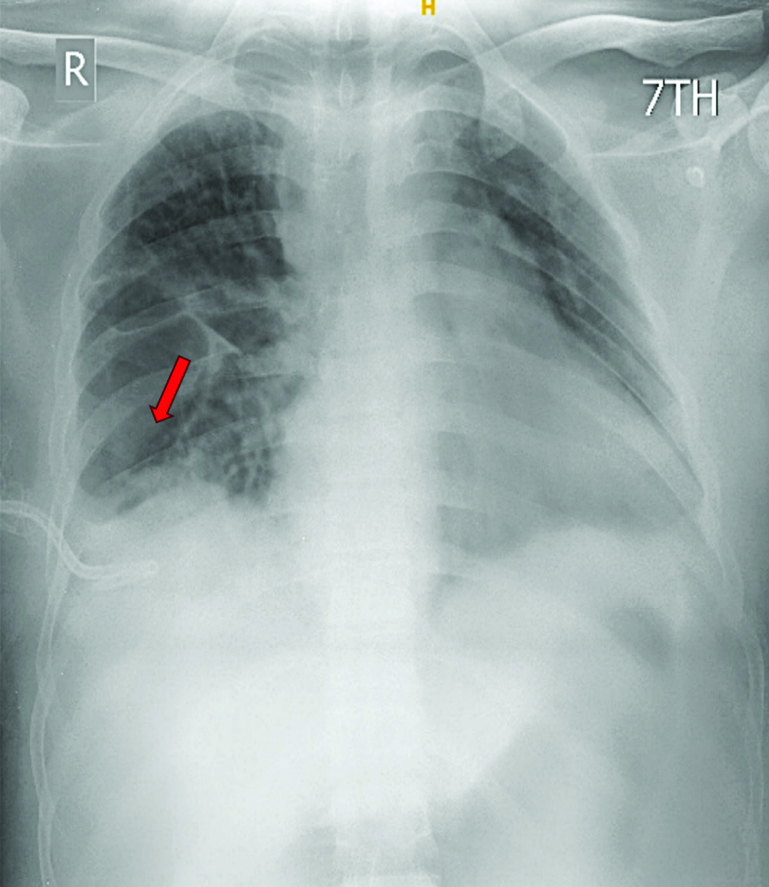

The patient was diagnosed with right loculated pleural effusion-haemothorax and congenital heart disease with Eisenmenger syndrome. Initial management included the insertion of a right-sided 14 F pigtail catheter, intravenous antibiotics, adequate analgesia and oxygen therapy. However, the initial drainage post-pigtail insertion was minimal (100 mL) [Table/Fig-5]. Due to the lack of subsequent drainage, even after reconfirming the tube position and patience, the patient was administered IPFT with 2.5 lac IU STK. The first cycle of IPFT resulted in 1150 mL of drainage, with a cumulative drainage of 2250 mL after three days [Table/Fig-6,7].

Chest X-ray showing right-sided pleural effusion (blue arrow) with pigtail in-situ (red arrow) prior to Intrapleural Fibrinolytic Therapy (IPFT).

Chest X-ray three days post Intrapleural Fibrinolytic Therapy (IPFT) showing resolution of effusion (red arrow).